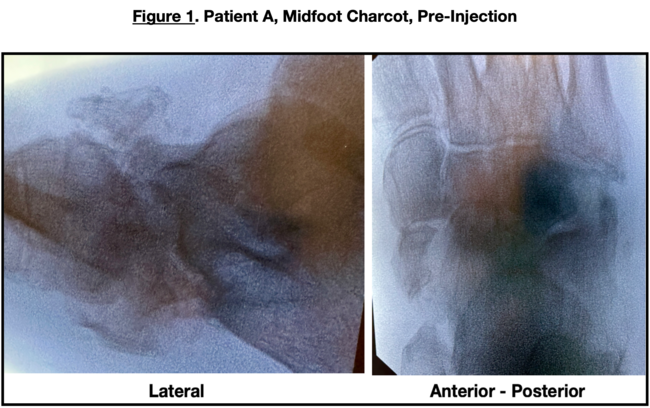

X-ray examination (Figure 1) revealed osteolysis and the midtarsal, talonavicular, and calcaneocuboid joint collapse. Computed tomography (CT) scans confirmed Charcot ununited fractures at the talonavicular joint with dorsal fragmentation of the navicular.